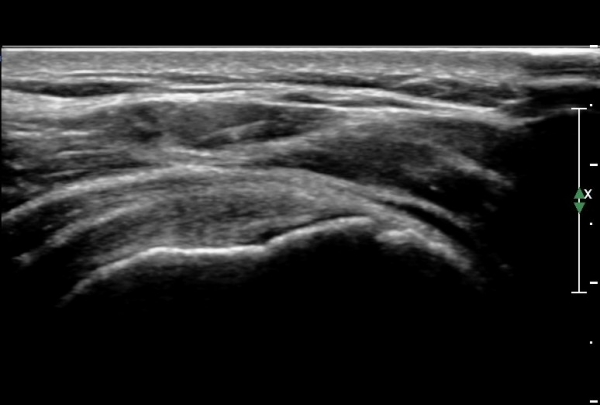

±Ø»ó°Ç Á¾´Ü¸é°Ë»ç¿¡¼­ ±Ø»ó°Ç ½ÉÃþÀÇ °Ç¿° ¼Ò°ß°ú Á¡¾×³¶³» ¼ö¾×Àú·ù°¡ °üÂûµÊ(»çÁø 7, 9).

ÀÌµÎ¹Ú±Ù°Ç Á¾´Ü¸é°Ë»ç¿¡¼­ Á¡¾×³¶³» ¼ö¾×Àú·ù´Â ´õ¿í ¶Ñ·ÈÇÔ(»çÁø 10).